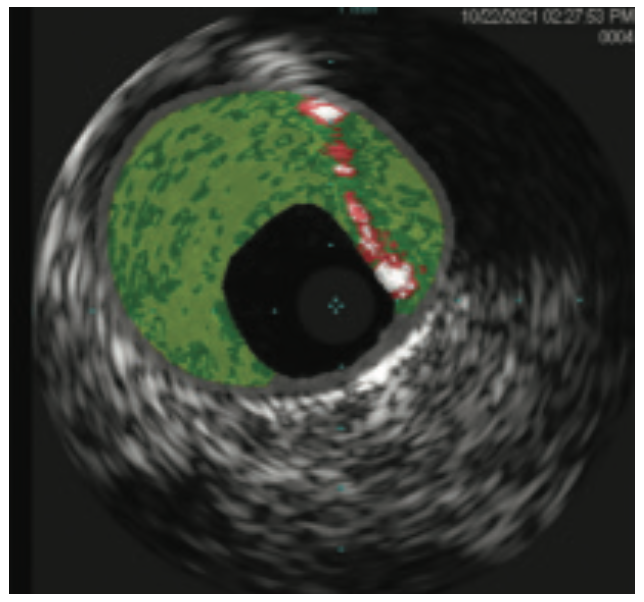

Imaging: Although the diagnostic radiographic imaging demonstrated a calcified lesion in the left main (LM) coronary artery, the type of lesion and the degree of stenosis were very hard to determine angiographically. Intravascular ultrasound (IVUS) performed within the LM artery showed that the lesion was nodular in nature and was as much as 70% stenosed.

The left main artery was cannulated with a 6 Fr XBLAD 3.5 guiding catheter (Cordis). The Whisper wire was used to cross the stenosis. IVUS was performed using an .014 Eagle Eye Platinum ultrasound catheter (Philips Volcano). In the same fashion as the RCA, the Whisper wire was exchanged for the ViperWire. The LM was subsequently treated with orbital atherectomy. Multiple passes were performed in opposition to the 70% nodular, calcified lesion that was fully identified on IVUS imaging. Once luminal gain was identified angiographically in the LM, the atherectomy crown was traversed distally into the calcified lesion in the proximal LAD. After two passes in the proximal LAD, the crown was traversed into the mid LAD lesion at the level of the first diagonal branch. Orbital atherectomy was again performed, reducing the calcium burden in both the LAD and the ostium of the diagonal branch. Balloon angioplasty was performed from mid LAD retrograde to the LM using a 3.0 mm x 20 mm NC Trek balloon. Following the balloon angioplasty, drug-eluting stents (3.0 mm x 15 mm Xience Skypoint, 3.5 mm x 38 mm Xience Skypoint, and a 5.0 mm x 30 mm Resolute Onyx drug-eluting stent [Medtronic], placed distal to proximal) were deployed from the mid LAD proximally to the LM, covering the orbital atherectomy-treated zone. The patient remained hemodynamically stable throughout the procedure. A completion angiogram was obtained. No slow flow or dissections were noted.